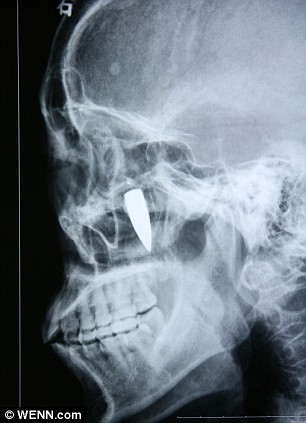

A Chinese woman suffering from chronic headaches discovered she had had a 3.3 cm long bullet lodged in her face, next to her ear, for 42 years!

When doctors showed the 65-year-old the pictures she told them she had no idea how the bullet could have got there. Then she recalled being injured during China's Cultural Revolution in 1967 when someone fired a pistol next to her head during a protest. Clickable.